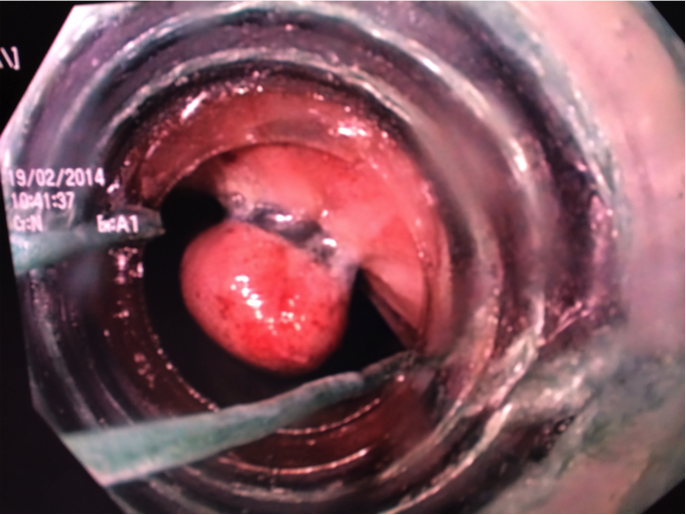

Figure 2 A black elastic rubber band ligator just applied on a pile column by a video colonoscope using the forward approach.